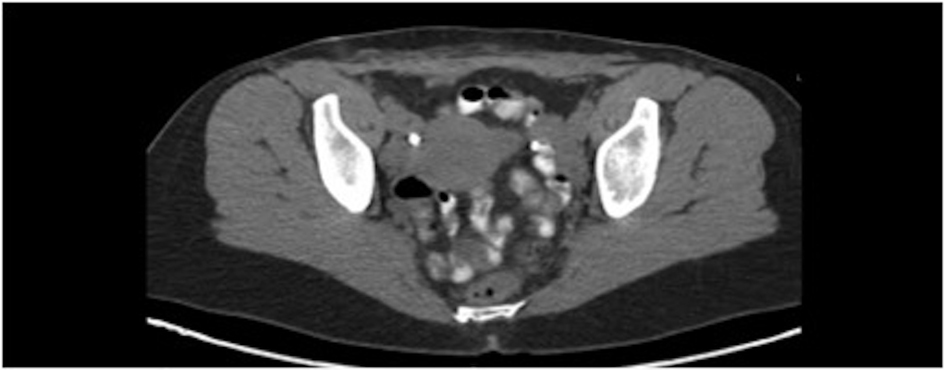

The patient initially underwent resection of the mass and given that a sarcoma was suspected, her wound was left open while tumor margins were obtained. The posterior tumor margin returned positive at three millimeters and a reexcision with subsequent wound closer was performed. The initial biopsy report suggested Ewing’s sarcoma/Primitive Neuroectodermal Tumor with findings concerning for melanoma. A EWSR-1 gene rearrangement and BRAF V600E mutation were then sent to confirm ES/PNET and melanoma respectively. A PET-CT revealed hypermetabolic activity with soft tissue stranding in the subcutaneous region of the anterior pelvis, bilateral pelvic and inguinal hypermetabolic lymph nodes, and a four-millimeter left apical lung nodule (Fig. 2, 3). These findings were concerning for a metabolically active neoplasm.

![]() Click for large image | Figure 2. Pelvic CT with abdominal wall soft tissue stranding after tumor resection. |

![]() Click for large image | Figure 3. PET CT with hypermetabolic activity with abdominal wall soft tissue stranding and pelvic/inguinal hypermetabolic lymphadenopathy. |